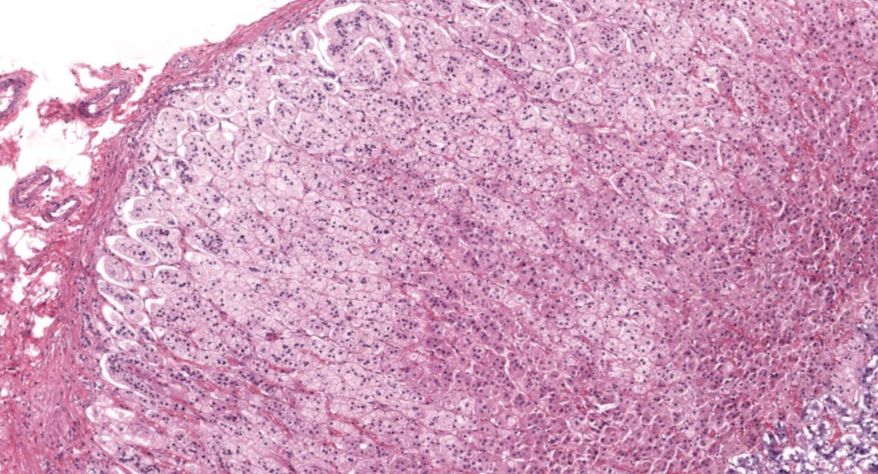

甲状腺

1.全景图